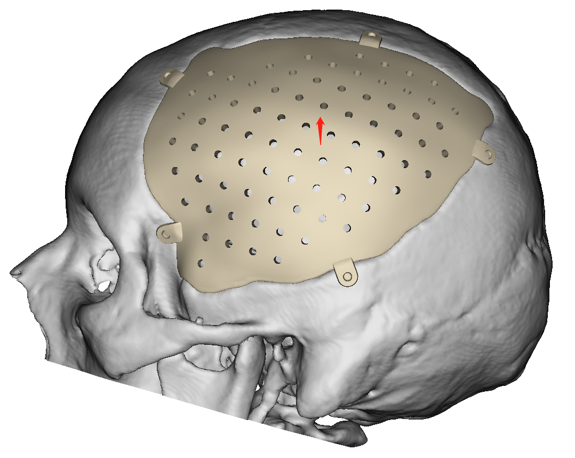

CASO CLÍNICO

Paciente masculino con un defecto de dimensiones aproximadas de 157.20×109.25mm el cual se reconstruyo con un implante en Peek.

Puente Saliente

Pacientes con mala calidad ósea.